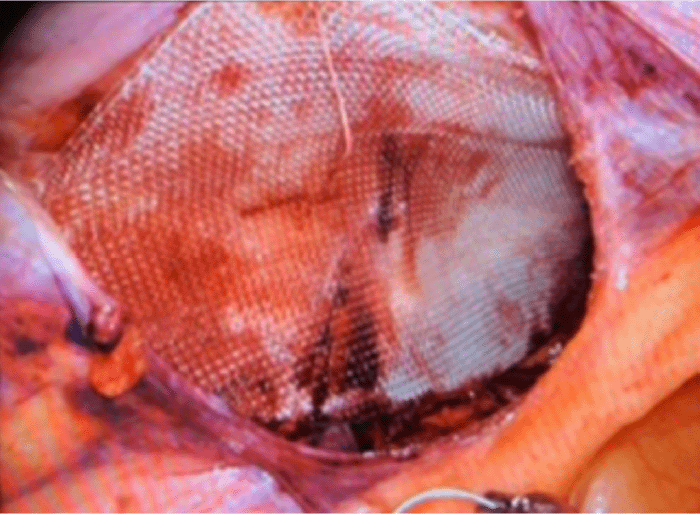

Figure 4. 3D Max Mesh Placement. Published with Permission

The patient was taken to the operating room for a da Vinci Xi robotic bilateral inguinal herniorrhaphy. The patient was placed under general endotracheal anesthesia, underwent transverse abdominis plane (TAP) blocks, and a robotic-assisted transabdominal preperitoneal (TAPP) approach was utilized. After docking the robot, invaginations of the peritoneum in the bilateral inguinal region representing bilateral inguinal hernias were noted as well as by the femoral and obturator orifices bilaterally. Beginning on the right, the peritoneum was opened from the anterior superior iliac spine to the medial umbilical ligament directly above the aforementioned invagination of the peritoneum. Superior and inferior peritoneal flaps were dissected, and the bladder was bluntly taken down to the midline, providing excellent visualization of the critical view of the myopectineal orifice (Figure 1) and the space of Retzius (Figure 2). In accordance with the European Hernia Society groin hernia classification,11 upon taking down the bladder, an incarcerated size 2 obturator hernia, a size 2 femoral hernia, a size 3 direct inguinal hernia, and a size 1 indirect inguinal defect containing hernia sac and lipomatous tissues were identified and reduced while avoiding any contact with the spermatic cord structures (Figures 3). A 3D Max Mesh was placed in the right preperitoneal space and, using 2-0 Vicryl, was secured to Cooper's ligament in the midline, superior medially to the rectus, directly above the defect by about 1 cm, and superior laterally to the body wall (Figure 4). This secured the mesh in four locations, covering all four defects with coverage in all directions. The peritoneal flaps were closed with a running 3-0 absorbable V-Loc suture, and a primary peritoneal defect was repaired with a single interrupted suture (Figure 5). In the same fashion, the left-sided peritoneum was opened from lateral to medial above the defects, peritoneal flaps were created, and the bladder was taken down to the midline. After this, a size 2 obturator hernia, a size 2 femoral hernia, a size 3 direct inguinal hernia, and a size 1 indirect inguinal defect containing the hernia sac and lipomatous tissues were identified, which were reduced. A 3D Max mesh was placed in the preperitoneal space and fixated in the same fashion as the right. Peritoneal flaps were covered with a running 3-0 absorbable V-Loc suture. The robot was undocked, ports were removed under direct vision, and the incised tissue was closed with absorbable sutures.